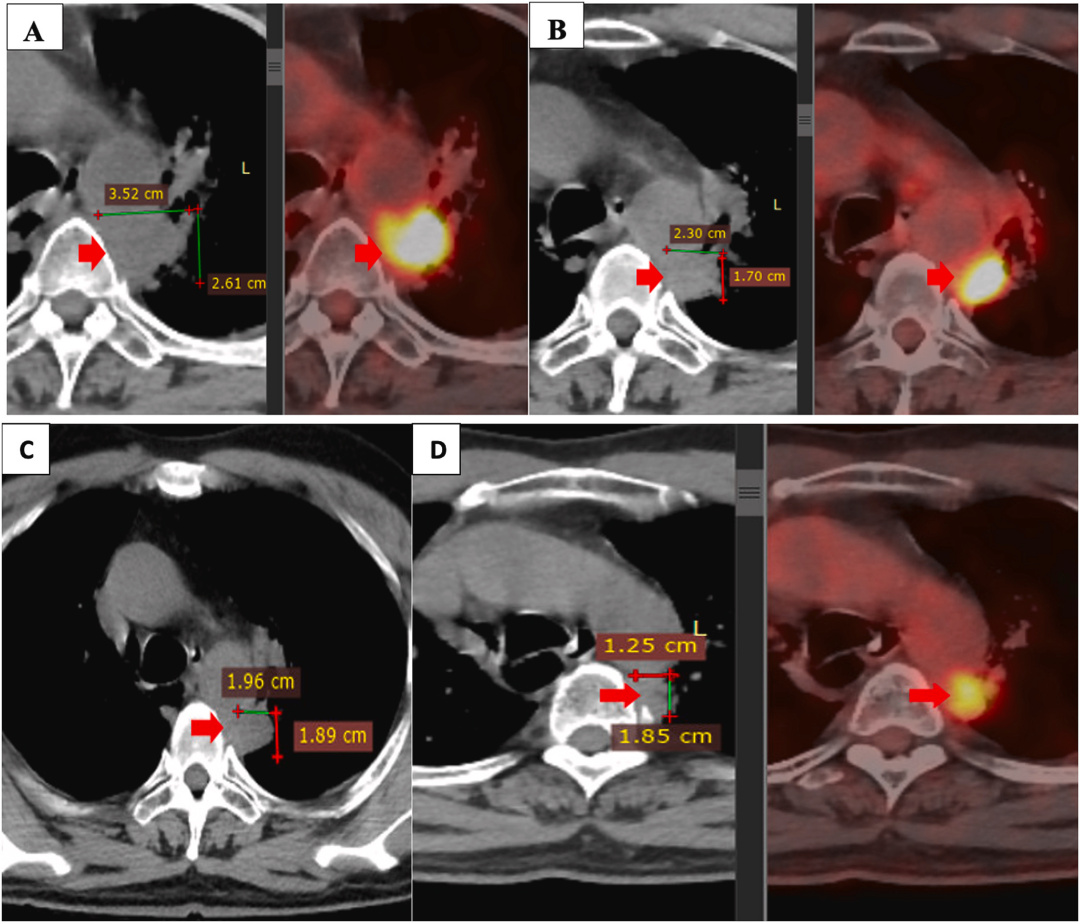

联合治疗前后的原发肿瘤大小(A:二线治疗后原发肿瘤进展;B:联合NK细胞治疗结束时;C、D:联合治疗结束3个月、6个月后)

由于疾病进展,患者的治疗方案发生了变化。2020年10月,患者住院与吉西他滨/阿瓦斯汀联合治疗,并接受了6个疗程(每个疗程1次输注)的NK(自然杀伤) 细胞治疗,每3周输注一次,输注6次。治疗期间,他经历了干咳和左胸疼痛。包括血液学和血液生化在内的临床辅助检查结果正常,但白细胞除外(2.81 g/L,低于正常值)。

联合治疗4.5个月后,患者干咳、胸痛症状消失,饮食摄入改善,生活质量明显改善。在使用联合治疗期间未观察到明显的副作用,肝肾功能评估在正常范围内。

2021年3月和2021年9月的PET/CT扫描显示,与原发肿瘤的大小相比,该肿瘤大小缩小了近一半。此外,两侧纵隔淋巴结和锁骨上淋巴结消失。